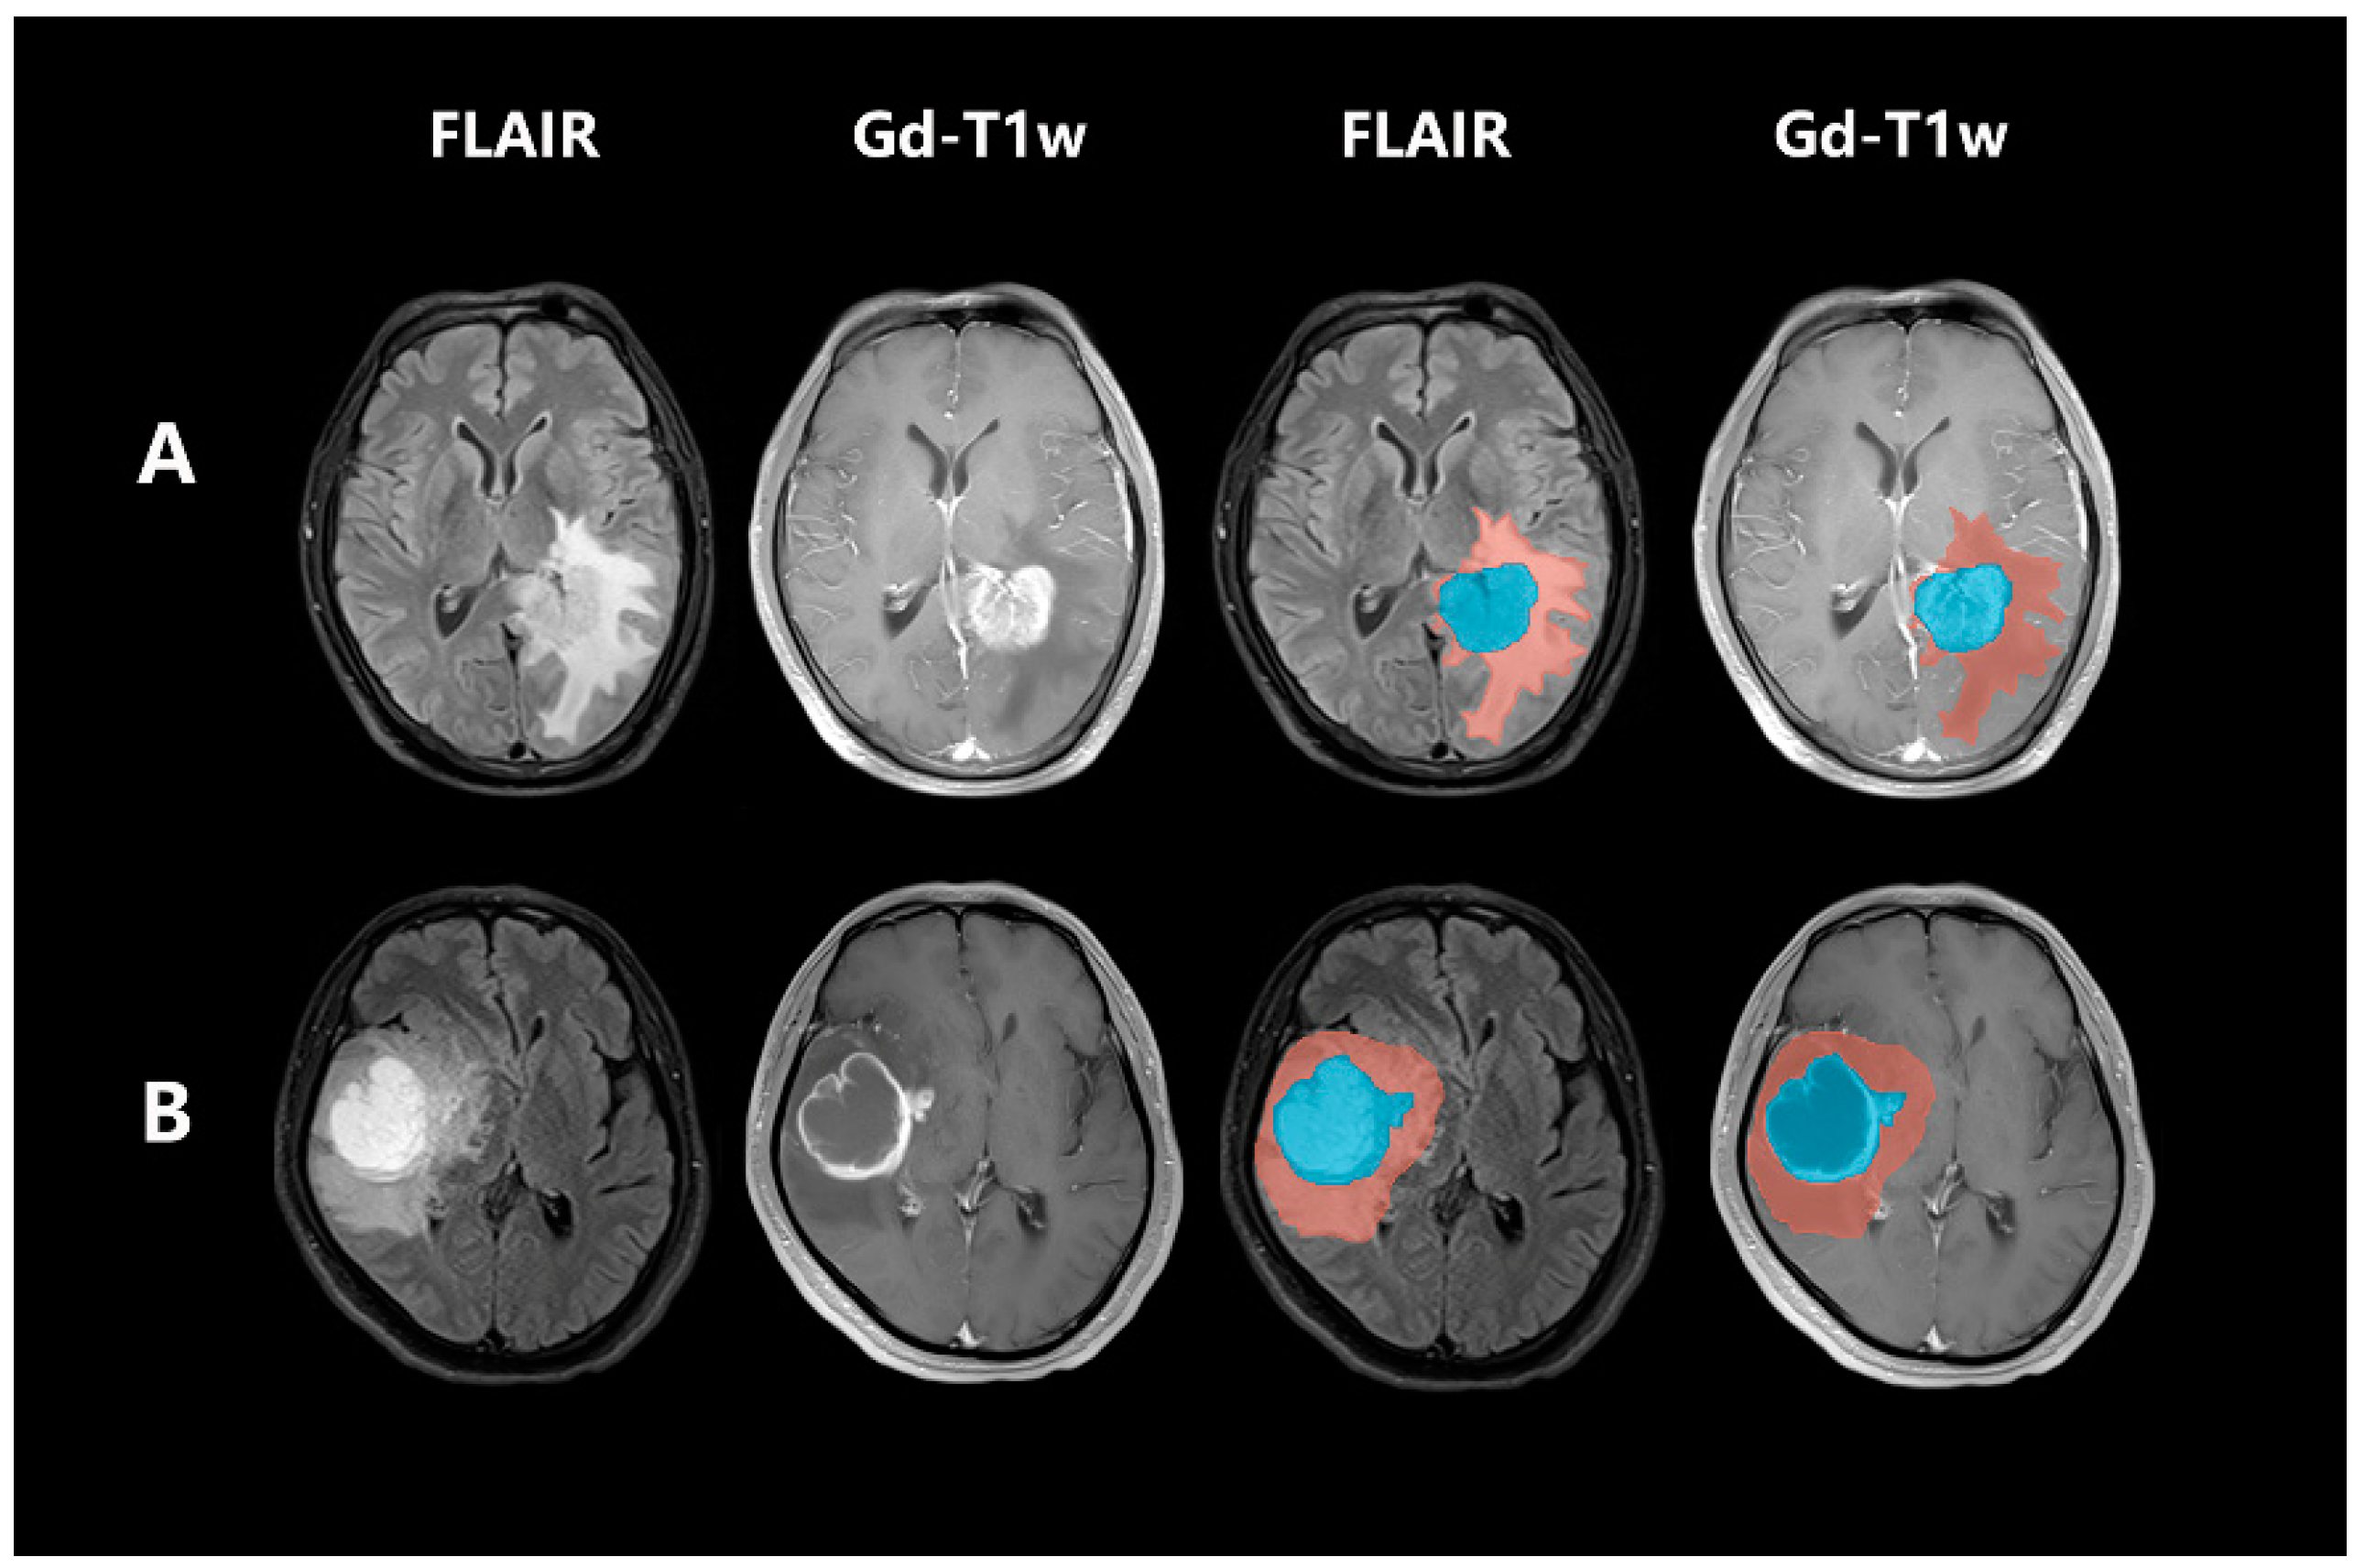

Figure 2.

The delineated and displayed regions of interest. Blue indicates the tumor parenchyma and orange indicates the edematous region. (A) Patients without CDKN2A/B homozygous deletion and (B) Patients with CDKN2A/B homozygous deletion.